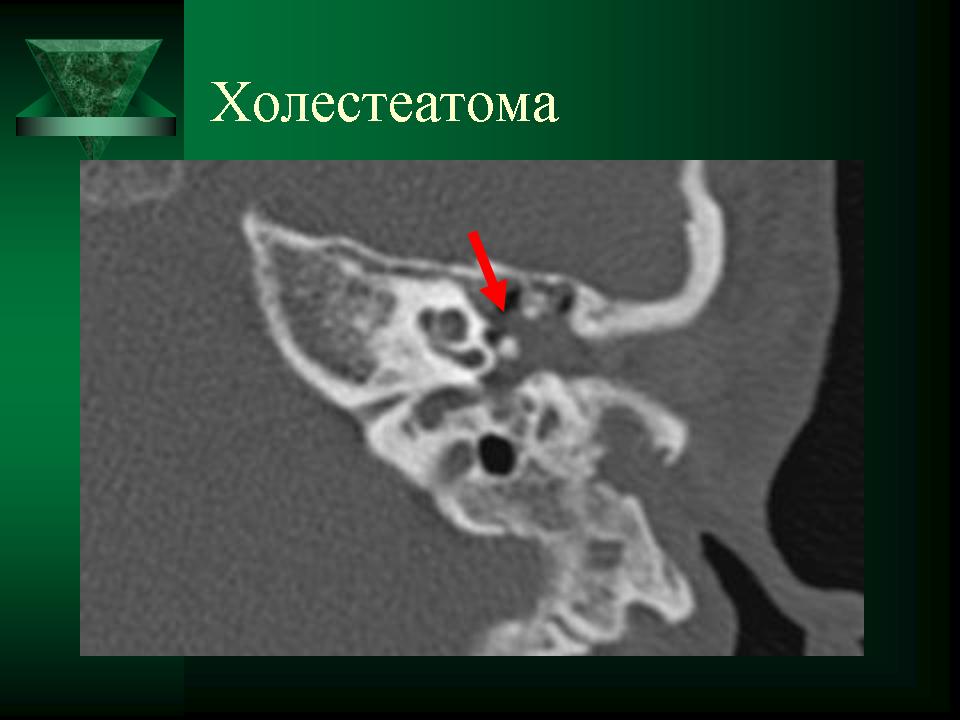

Диагностика холестеатомы представляет определенные трудности. Основными методами выявления холестеатомы последние несколько десятилетий остаются отоскопия (отомикроскопия) и рентгенологические методы (рентгенография в различных укладках и компьютерная томография). Компьютерная томография височных костей позволяет диагностировать холестеатому намного чаще, чем обычная рентгенография, однако степень достоверности данной диагностики остается невысокой, так как плотность холестеатомы практически соответствует плотности грануляционной ткани. Поэтому чувствительность метода КТ в диагностике холестеатомы составляет всего 71% при специфичности 55% [50]. Кроме того, следует учитывать, что указанный метод требует не только дорогостоящего оборудования, но и высококвалифицированных рентгенологов со специальной подготовкой, позволяющей им правильно интерпретировать полученные результаты.

2. Применение компьютерной томографии позволяет повысить степень обнаружения патологического процесса до 90% случаев, однако не позволяет достоверно дифференцировать холестеатому и грануляционную ткань по причине низкой специфичности метода (55%).

ID: 9409 Cholesteatoma Dr Frank Gaillard - 14 Apr 2010 Cholesteatoma, path proven.

ID: 9408 Cholesteatoma Dr Frank Gaillard - 14 Apr 2010 HistologyFragments of keratin debris and benign squamous epithelium, con...

ID: 5467 Cholesteatoma - acquired Dr Frank Gaillard - 26 Jan 2009 CT through the temporal bone demonstrates a soft tissue mass in Prussak'...